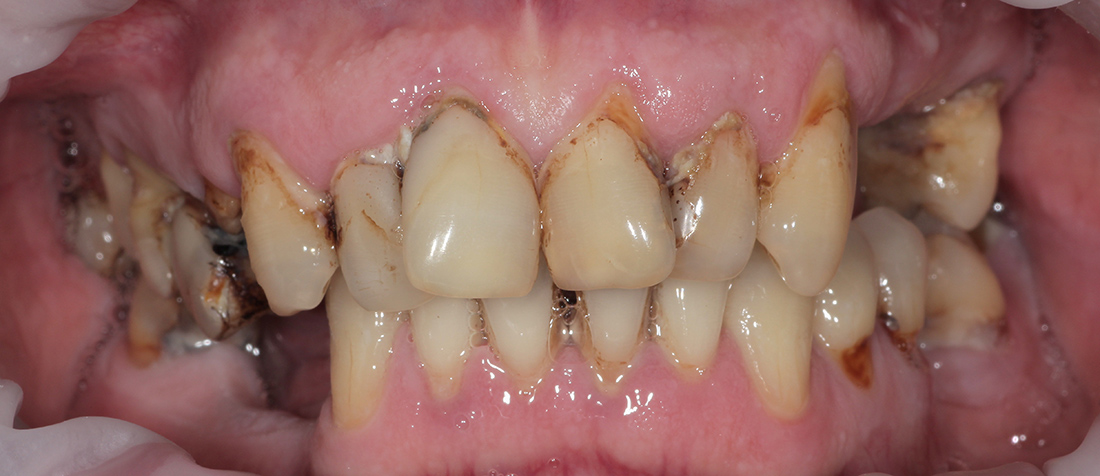

Очень сложная ситуация

Пациент М., 53 года. Очень сложная ситуация изначально... После обсуждения вариантов лечения мы пришли к следующему плану лечения.